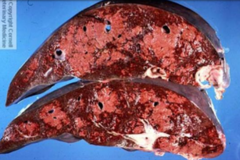

Nutmeg Liver (Fatty Change)

Front

Back